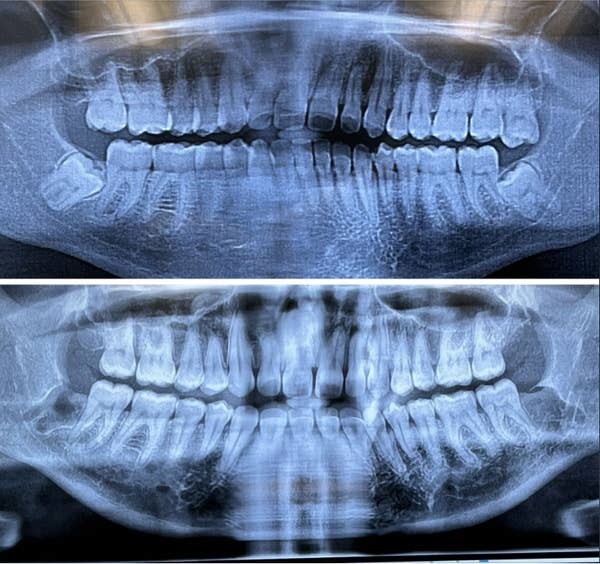

24. Неделя до удаления зубов мудрости и неделя после